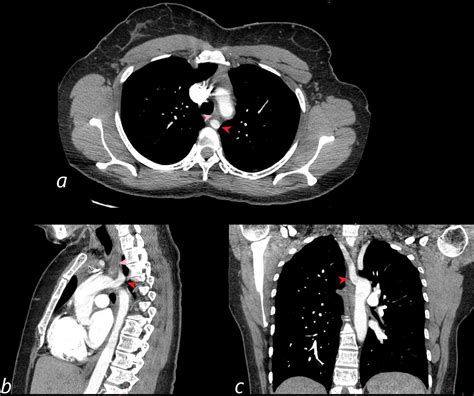

The diagnosis of ARSA involves a combination of clinical evaluation and imaging studies. The following diagnostic modalities are commonly used:

• Chest X-ray: May show an abnormal aortic arch contour or a right-sided aortic knob.

• Barium Swallow: Can demonstrate an indentation on the posterior wall of the esophagus, suggestive of an aberrant vessel.

• Computed Tomography Angiography (CTA): Provides detailed images of the aortic arch and its branches, confirming the diagnosis and defining the course of the aberrant artery.

• Magnetic Resonance Angiography (MRA): Offers a non-invasive method to visualize the vascular anatomy, particularly useful in pediatric patients.

• Echocardiography: Can be used to assess associated cardiac anomalies and evaluate the aortic arch.

Imaging studies are crucial for planning surgical intervention, if necessary.